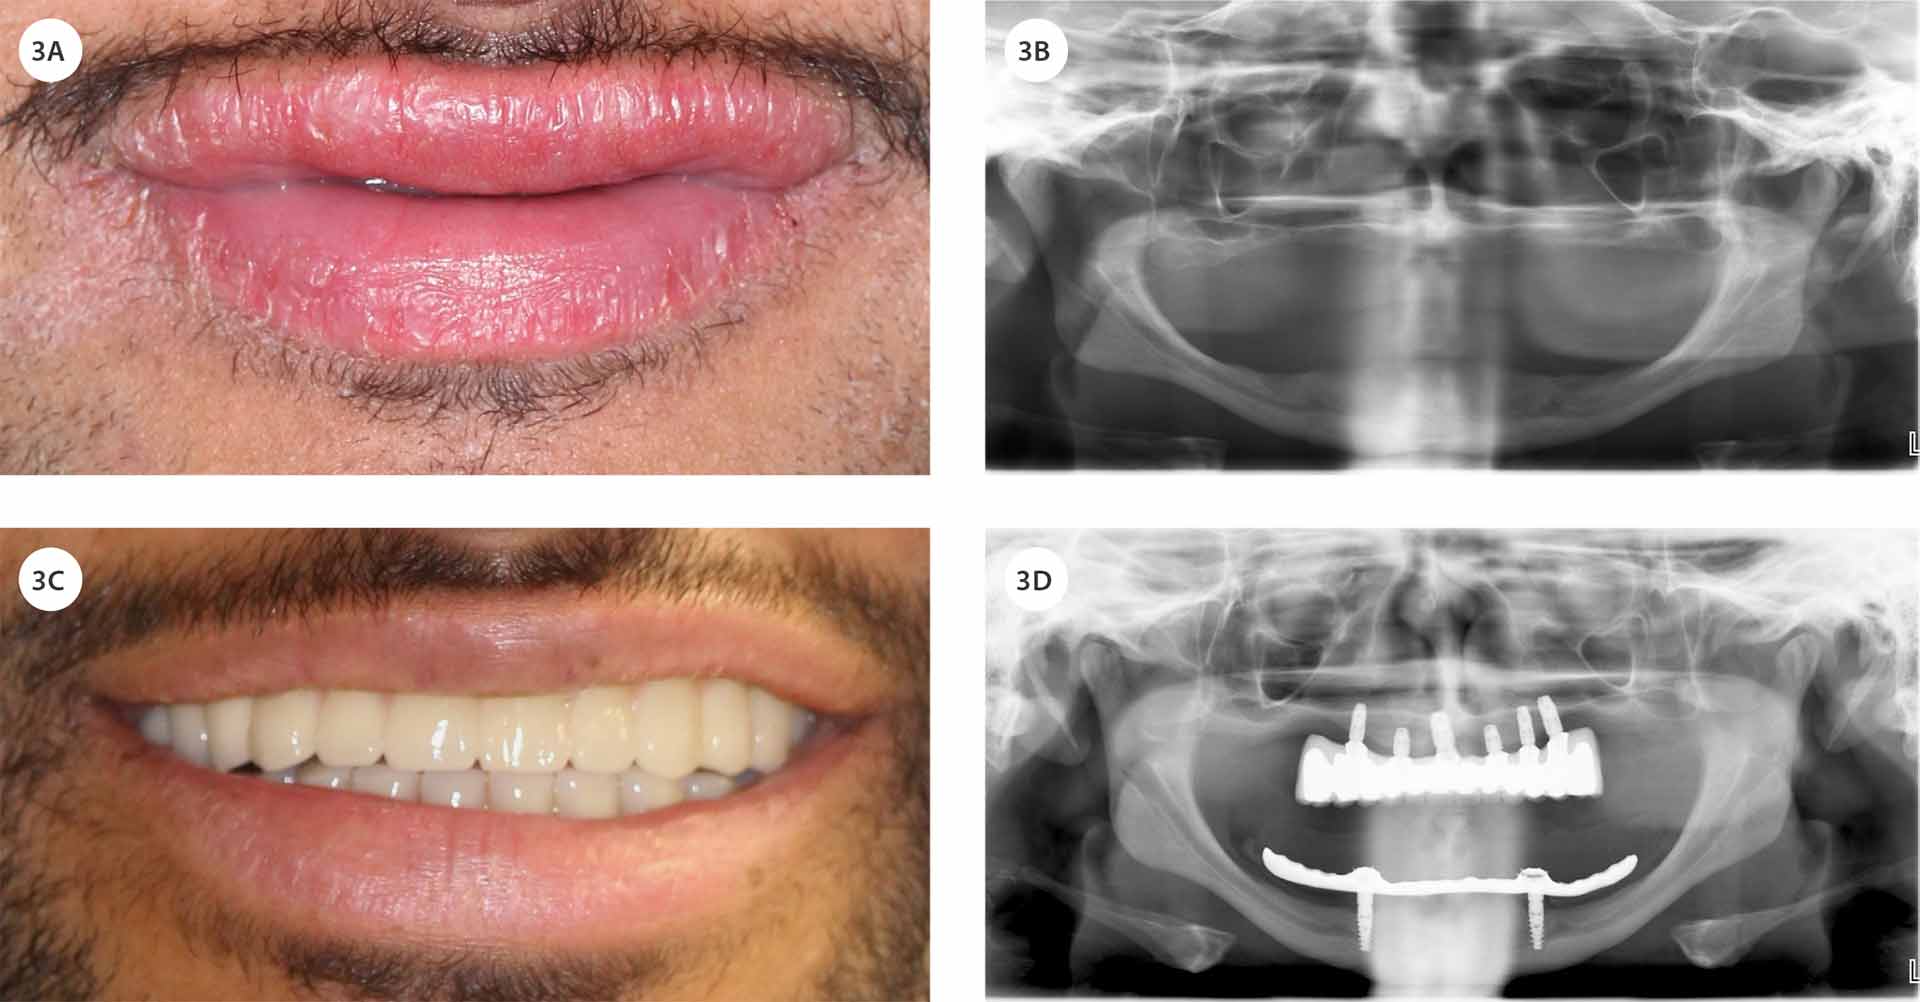

Omtrent seks måneder etter implantatinnsettingen i underkjeven ble det tilpasset en dekkprotese. Deretter ble det utført en bentransplantasjon under generell anestesi, hvor en kortikal og spongiøs benblokk cirka 15 × 20 × 55 mm ble høstet fra høyre hoftekam og transplantert til overkjeven (figur 2B). Fem måneder etter transplantasjonen ble seks Asta EV-implantater installert i overkjeven, og ytterligere fire måneder senere ble det fremstilt og innpasset en implantatbro (figur 3C, 3D). Pasienten rapporterte høy grad av tilfredshet med det endelige behandlingsresultatet, som imøtekom både funksjonelle behov og estetiske forventninger (figur 3C).

Figur 3. Smil og OPG før (A, B) og etter (C, D) behandling med implantatbro i overkjeven og dekkprotese i underkjeven.

Rehabiliteringen av pasientens tannstatus, gjennom et samarbeid mellom kjevekirurgisk seksjon og den behandlende tannlegen, resulterte i et vellykket behandlingsforløp. Sammenlignet med pasientens tidligere situasjon – preget av redusert tyggefunksjon og et prematurt aldrende ansiktsuttrykk som følge av langvarig tannløshet – medførte tiltakene en markant forbedring i både livskvalitet og pasientens egenopplevde estetiske fremtoning.